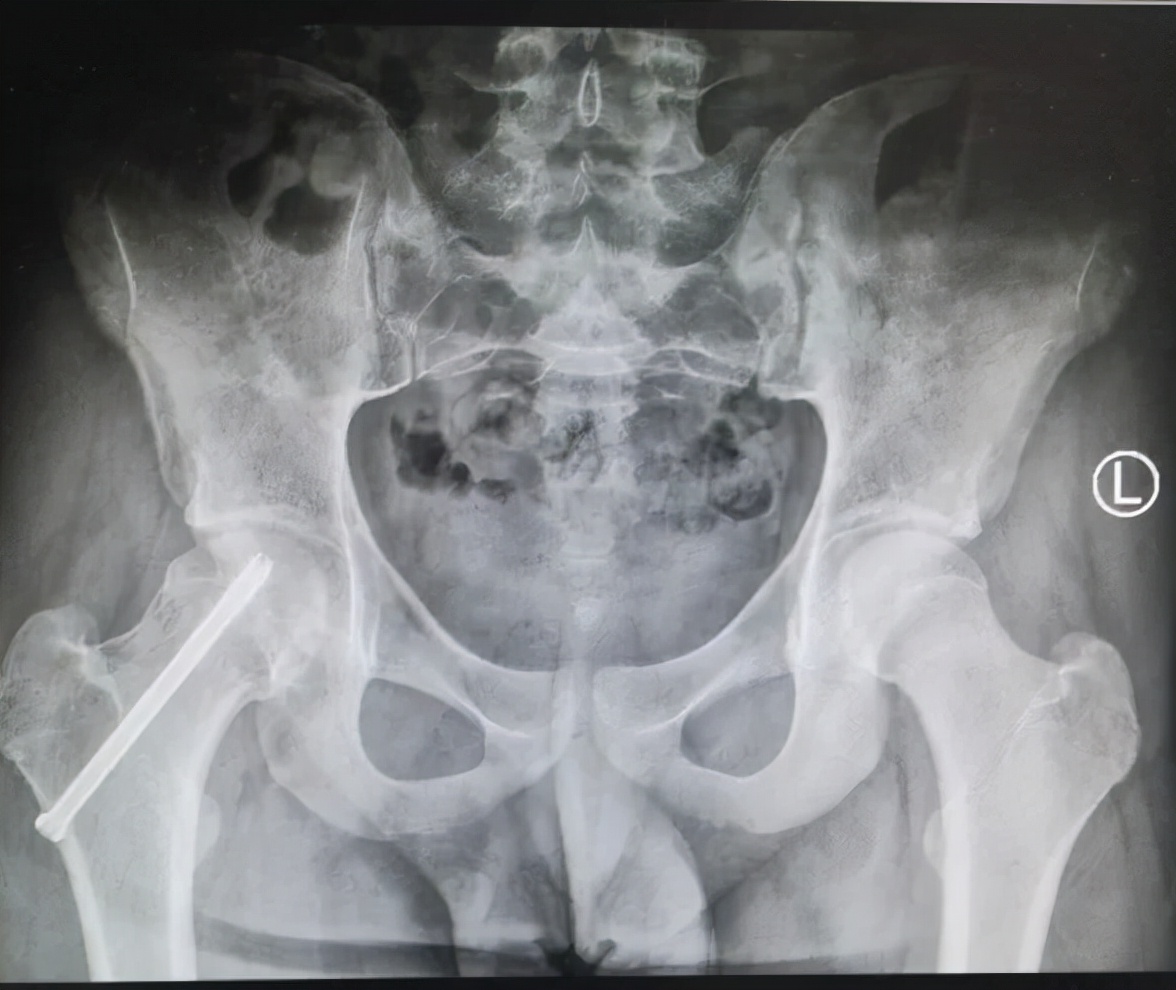

病例2 男,14岁,右侧重度SCFE,行闭合复位,经皮空心钉固定术

病例2 术后17个月复查,X线示位置良好,无股骨头缺血坏死发生